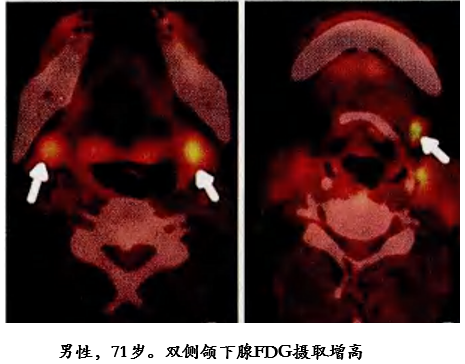

涎腺受累 PET-CT 表现

腹膜后纤维化

59 岁男性,增强 T1 显示腹主动脉前方软组织增厚,增强后病灶轻度强化。右侧肾盂及上段输尿管积水扩张,CT 增强显示双侧髂总动脉周围不规则软组织应包绕血管,右侧输尿管支架植入